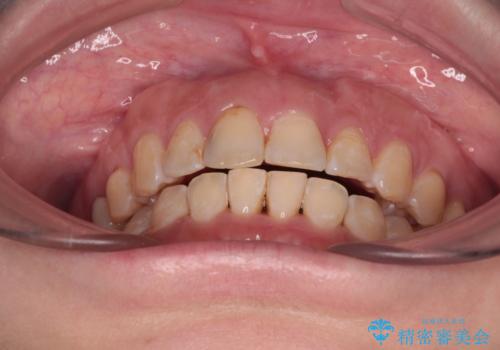

- 飛び出た上の前歯を気にして来院された患者様です。

奥歯の咬み合わせは、上顎歯列が理想的な一よりも数mm前方にある状態でした。

なるべく早めに治療を終えたいとのことで、補助装置を用いて上顎臼歯を後方に移動させ、同時にワイヤー装置にて整えることとしました。

舌の突出癖が原因で上下の歯に大きなスペースが生じていたため、舌のトレーニングをしっかり行っていただくことで、上顎歯列をスムーズに移動させることができました。